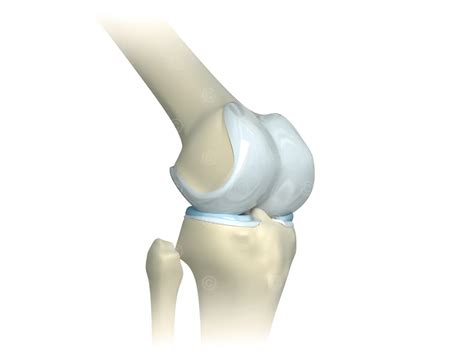

Detailed view of human knee anatomy

The cartilage found in the knee is primarily articular cartilage, a type of hyaline cartilage that covers the ends of the bones. Unlike other tissues in the body, it has a unique composition that allows it to withstand significant compressive forces. It consists of a dense network of collagen fibers and proteoglycans, which attract water to create a gel-like consistency.

Because knee joint cartilage is avascular—meaning it lacks a direct blood supply—it relies on synovial fluid to obtain nutrients and remove waste products. This process, known as imbibition, occurs during the compression and release cycles of movement, which is why consistent, low-impact exercise is essential for its health.